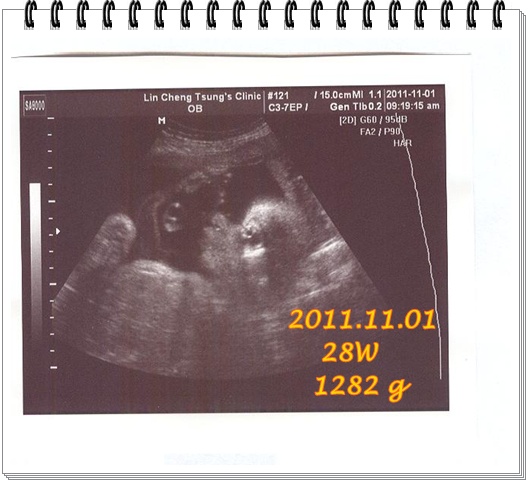

8/5又去產檢了,等了一個月再去看看我家二寶有沒有乖乖。

二寶今天剛好15週整。可以檢查中期唐氏症,所以今天麻麻被抽了一大管的血。